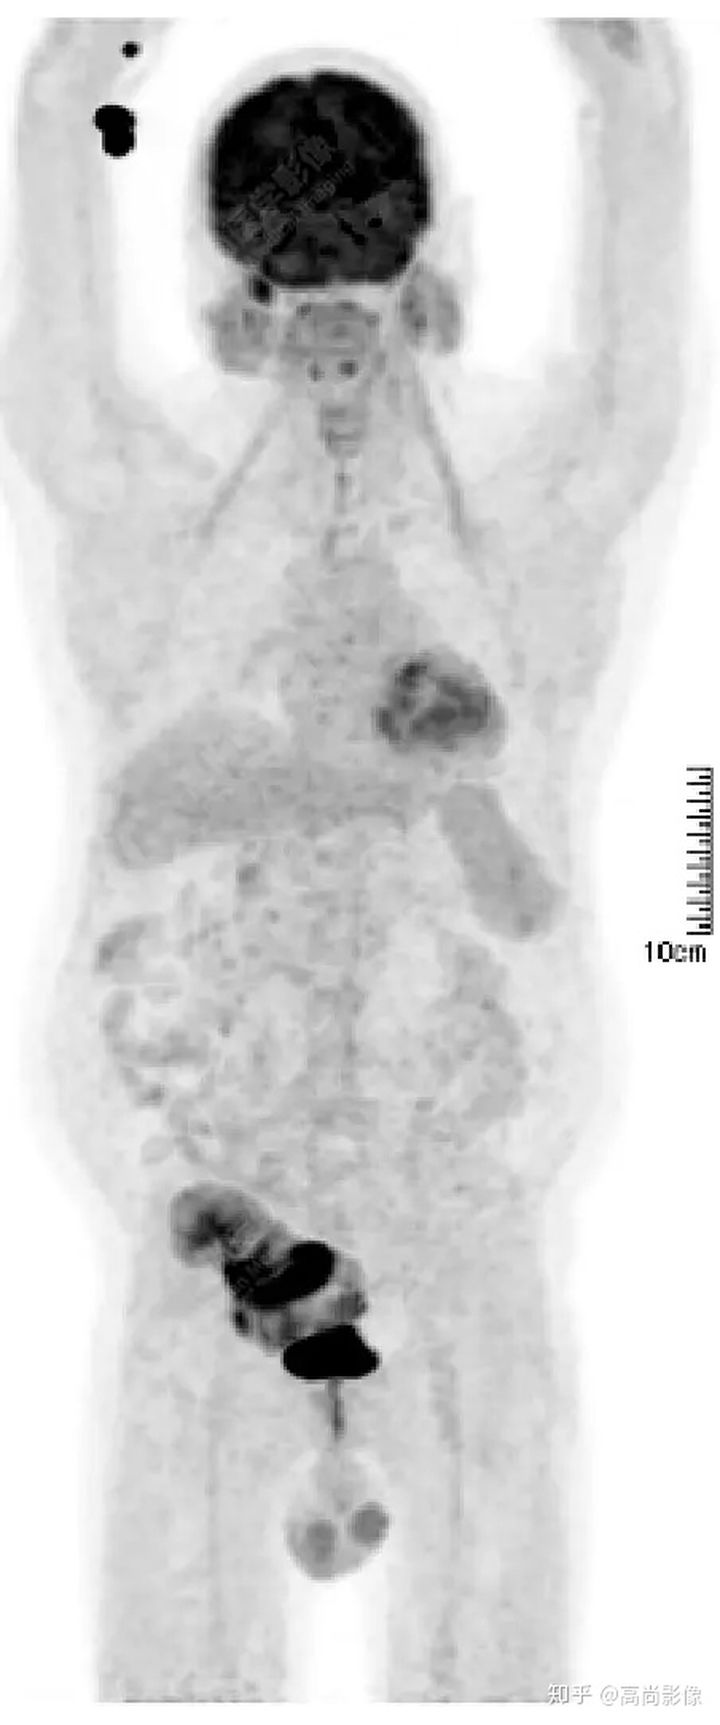

PET/CT檢查意義

發(fā)現(xiàn)全身其它部位有無結(jié)內(nèi)或結(jié)外淋巴瘤病灶。由于淋巴瘤組織多具備高代謝、大范圍無氧酵解的特性,葡萄糖需求量為正常組織細(xì)胞的20~30倍,正電子湮滅產(chǎn)生的光子信號(hào)聚集于灶區(qū),PET捕獲后可半定量分析其分布特征【4】。

PET/CT融合二者各自優(yōu)勢

將影像學(xué)技術(shù)提高到分子水平,結(jié)合以腫瘤形態(tài)學(xué)、解剖學(xué)、代謝學(xué)特征,對(duì)DLBCL細(xì)胞增殖、生長或凋亡可作出有效判斷,還可為檢驗(yàn)治療有效性與預(yù)后療法優(yōu)化提供指導(dǎo)【4】。